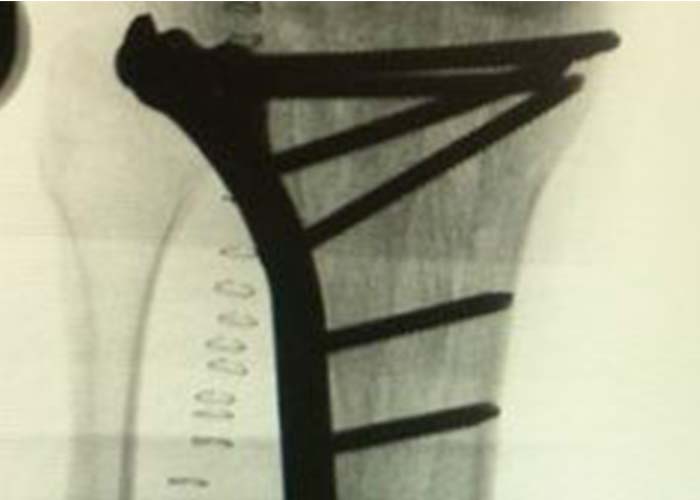

Operación

Es intervenido quirúrgicamente a las 48 horas realizándose abordaje anterolateral de tibia proximal, reducción y fijación interna con placa lateral de tornillos bloqueados y no bloqueados de 4,5 mm.